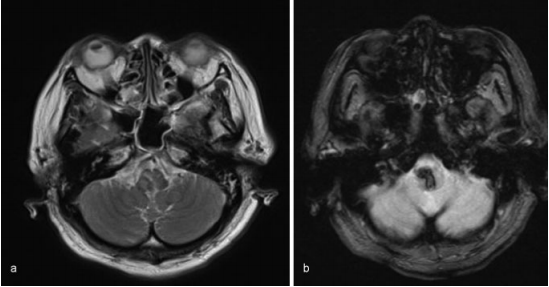

入院后,她出現(xiàn)白天呼吸抑制(每分鐘呼吸10次)和夜間呼吸暫停。然后她進(jìn)行插管,并用呼吸機(jī)控制呼吸。MRI未發(fā)現(xiàn)明顯的出血原因,如海綿狀畸形、動(dòng)靜脈畸形或腫瘤。患者隨后被診斷為高血壓原發(fā)性延髓出血,隨后通過持續(xù)靜脈輸入鈣通道阻滯劑來降低血壓。然而,病人的呼吸抑制沒有改善。

圖:磁共振圖像顯示出血沒有明顯的病理原因,(a)T2加權(quán)(b)T2加權(quán)。